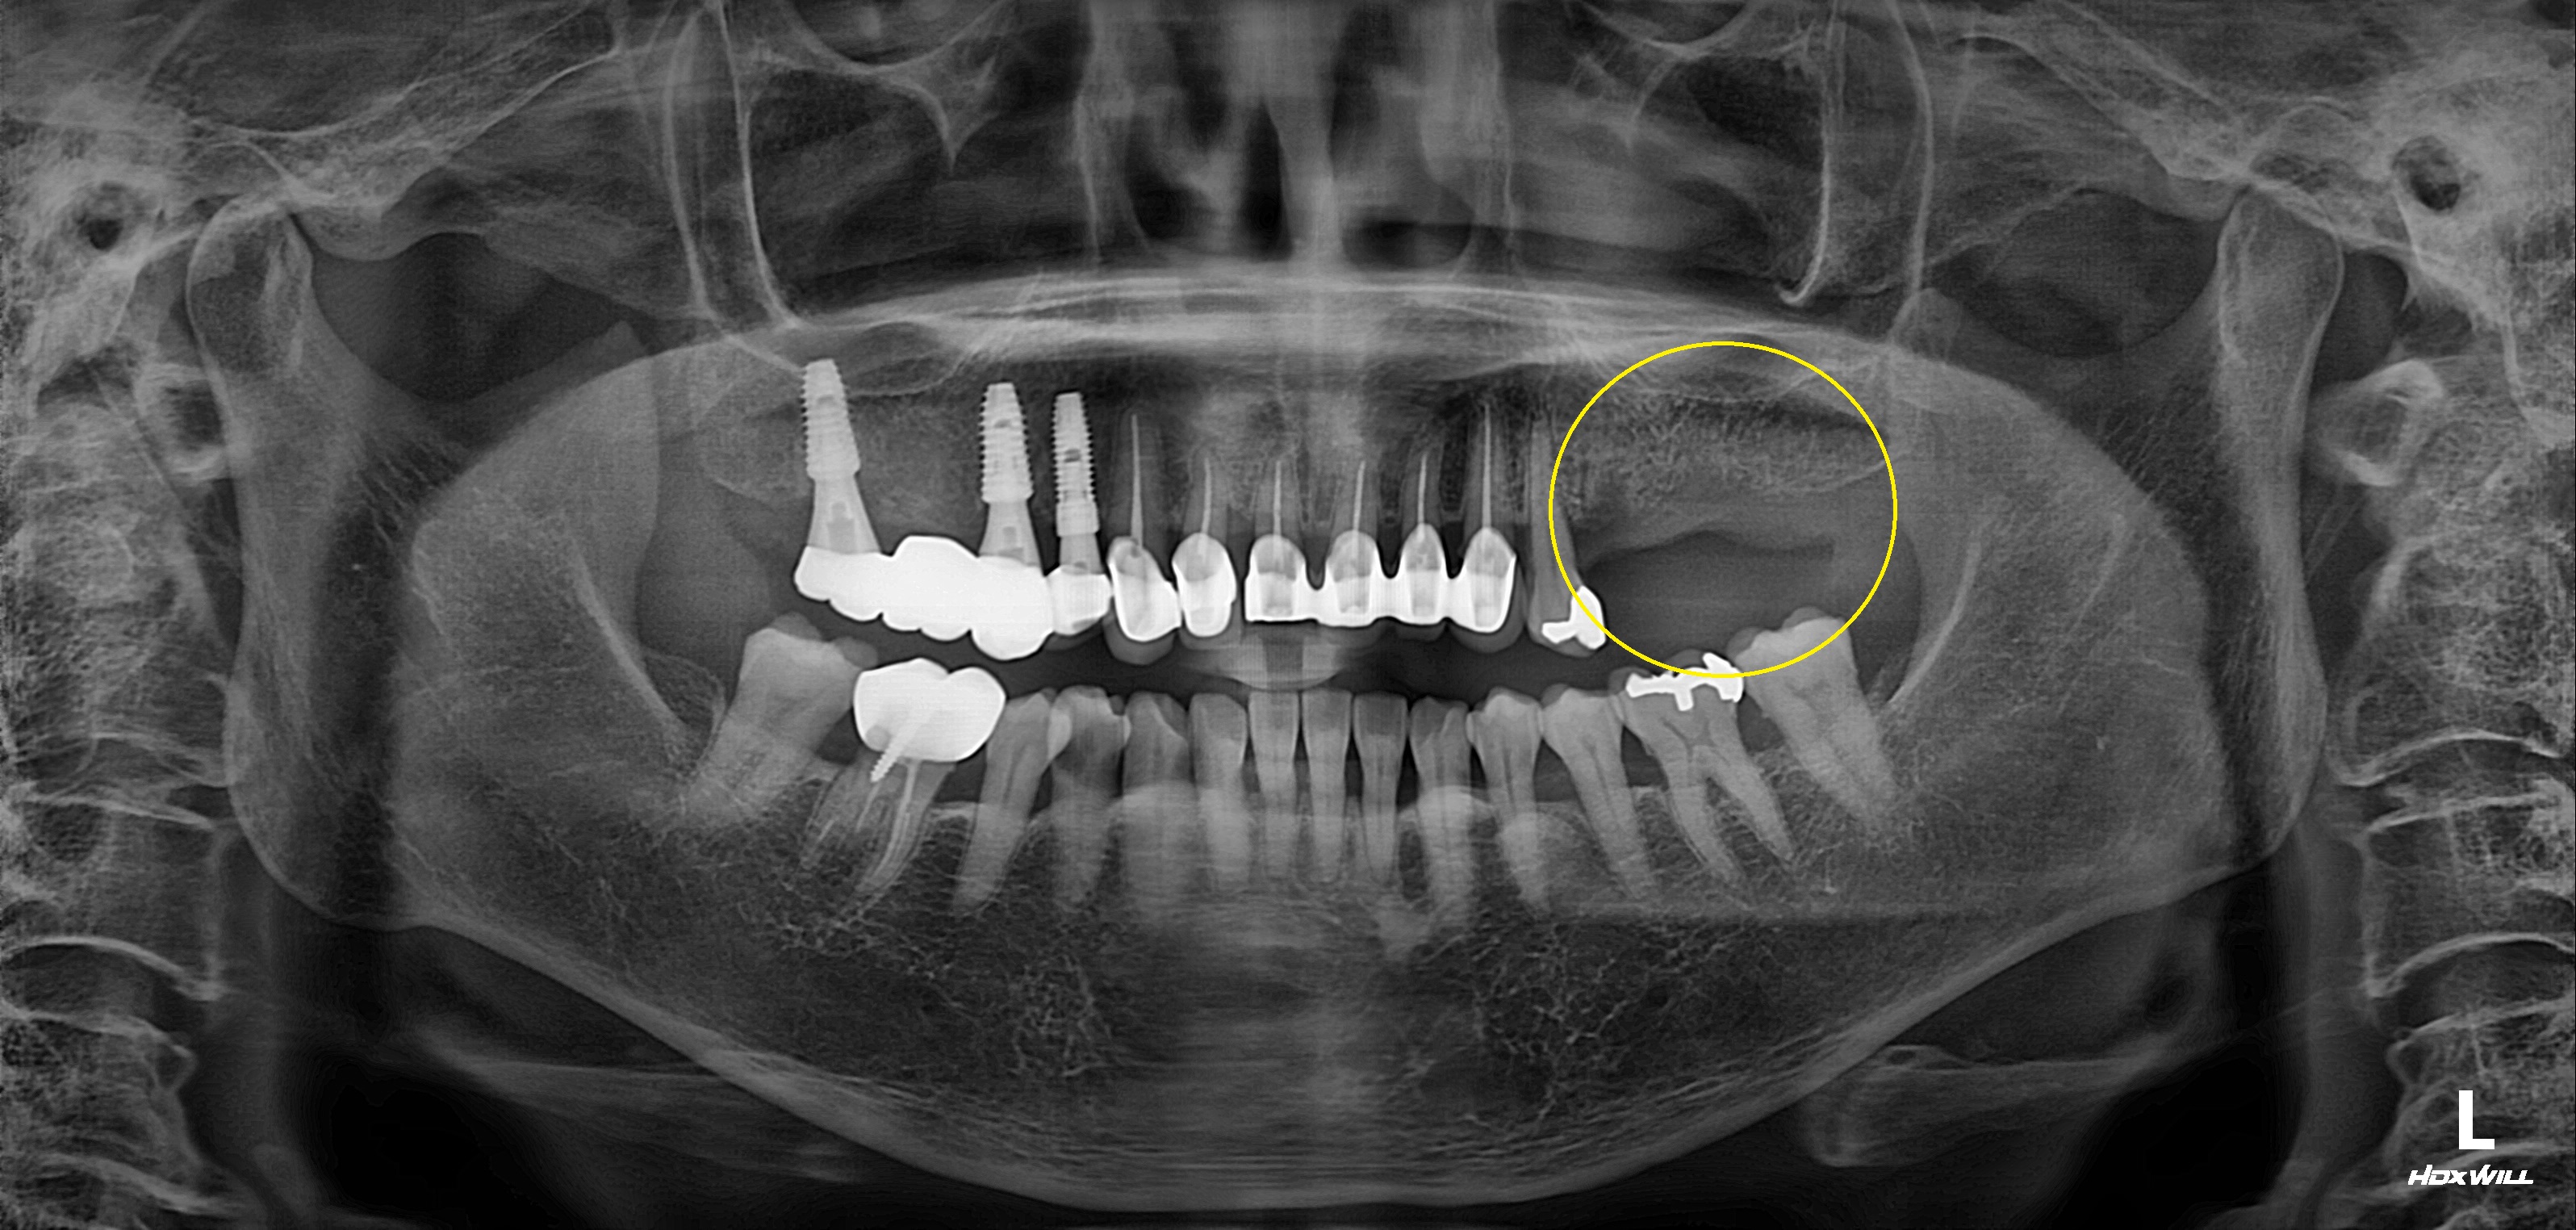

구치부 임플란트 식립사례

전후사진

완전매복치 발치 사례